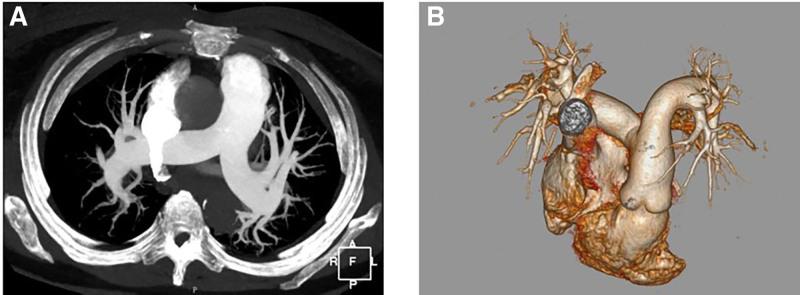

The patient was suspected of having PTTM with a pancreatic primary malignancy, based on admission findings including percutaneous oxygen saturation of 88%, respiratory alkalosis on blood-gas analysis, and elevated levels of d-dimer, NT-proBNP, and multiple tumor markers, combined with computed tomography angiography results showing enlarged lymph nodes (mediastinum, bilateral hila, right cardiophrenic angle, retroperitoneum) and a blurred peripancreatic space.

根据入院检查结果,包括经皮血氧饱和度为88%、血气分析显示呼吸性碱中毒、D-二聚体、N末端脑钠肽前体(NT-proBNP)和多种肿瘤标志物水平升高,结合计算机断层血管造影结果显示淋巴结肿大(纵隔、双侧肺门、右心膈角、腹膜后)以及胰腺周围间隙模糊,该患者被怀疑患有PTTM并伴有胰腺原发性恶性肿瘤。